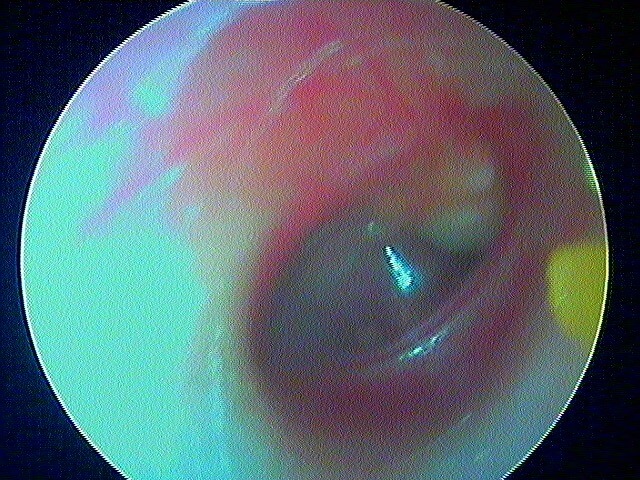

Ici des stades V perforés

3/2 barotraumatique

– stade I : hyperhémie du manche du marteau et de la pars flaccida ;

– stade II : tympan rétracté, congestif, immobile

– stade III : aspect d'otite séromuqueuse

– stade IV : aspect otite séro-hémorragique, otohématome

– stade V : perforation